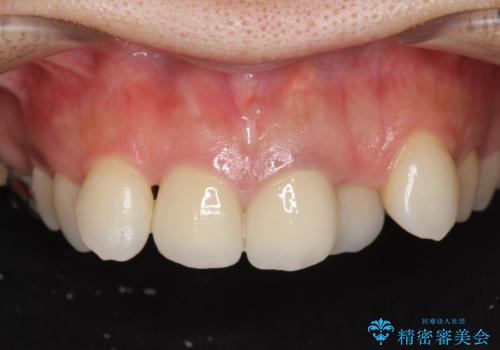

[前歯の変色] 前歯の見た目を改善したい

![[前歯の変色] 前歯の見た目を改善したいの症例 治療後](https://seimitsushinbi.jp/wp/wp-content/uploads/2021/05/1f01d9f0751d14a2f5d20ed7475c6e38-500x350.jpg?v=1622180216)